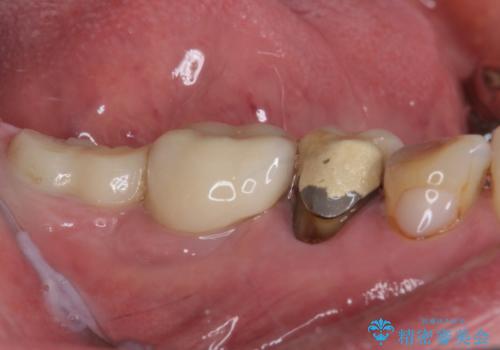

- 強い咬合力により表面のセラミックが剥がれ、裏打ちの金属が見えてしまっていることを気にして来院された患者様です。

仮歯に変えた後、咬合力に耐えることを目的に強化セラミッククラウンにて補綴することとしました。